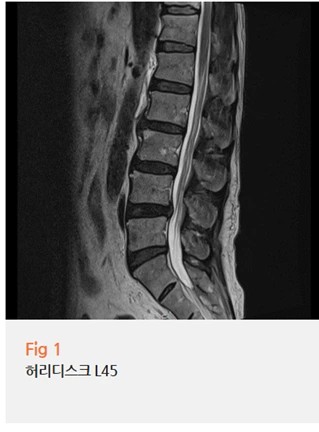

허리 MRI에서는 요추 4-5번 부위에서 추간판 탈출이 확인됐습니다.

그리고 혈관 초음파에서는...

왼쪽 천대퇴동맥이 60% 협착.

오른쪽 천대퇴동맥이 40% 협착.

왼쪽 종아리 저림이 오른쪽보다 훨씬 심했던 이유가

바로 이 수치 차이였어요.

혈관이 좁아지면 다리로 가는 혈류가 줄어들고,

특히 빠르게 걸을 때처럼 혈액 공급이 더 필요한 상황에서

산소와 영양이 제대로 전달되지 않으면서 저림과 통증이 오는 거예요.

걸을 때 심해지고 쉬면 나아지는 증상 패턴,

이게 바로 혈관성 파행의 전형적인 양상이에요.

여기에 요추 디스크까지 겹쳐있으니,

이 환자분 입장에서는 신경에서 오는 자극과 혈관에서 오는 허혈이

동시에 다리를 압박하고 있었던 셈이에요.